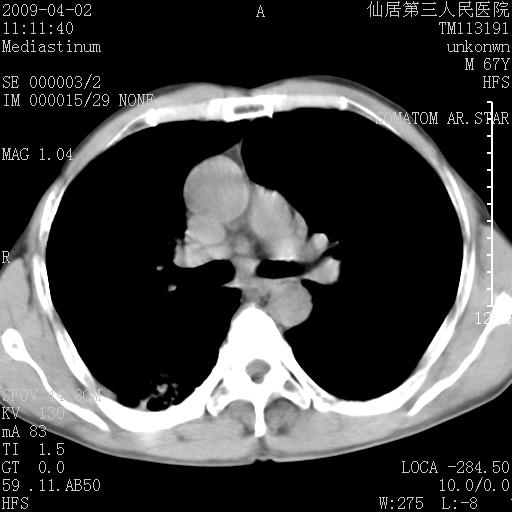

患者老年男性,乏力畏寒来诊,摄胸片示右下肺感染性病变,抗炎两周后复查胸片,无好转有进展。

后做ct平扫表现如下:

考虑右肺炎症可能性大,不除外细支气管肺泡癌

是否还要考虑肺间质纤维化,建议hrct扫描。

考虑间质性肺炎。

病灶呈蜂窝征,纵隔多个淋巴结肿大;肺泡癌需考虑

我认为普通的感染应该可以除外,间质性肺炎可能性较大,但如何解释纵膈的淋巴结肿大呢

考虑双肺间质性改变(间质纤维化?)伴右肺下叶感染。